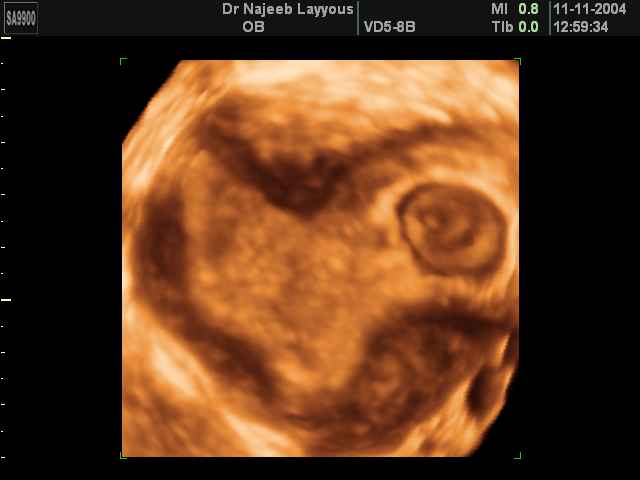

- لقطات فيديو للجنين بجهاز الموجات فوق صوتية رباعي الأبعاد

- صور للجنين في المراحل الأولى من الحمل

- صور جانبية لرأس الجنين